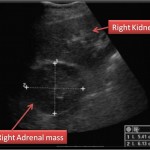

Ultrasound is sometimes used in the diagnosis of adrenal tumors. Ultrasounds use sound waves to form a picture of the inside of the body. At times, it can be difficult to tell if an adrenal tumor is an adenoma or a cancer. For tumors that are larger than 3 cm, ultrasound is a good method of telling the difference between the two.